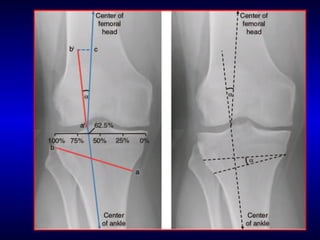

Important AxesImportant Axes

• Mech Axis (a):Mech Axis (a):

• center of kneecenter of knee  center of hipcenter of hip

• 0-2.20-2.2° valgus° valgus

• Anat Axis (b):Anat Axis (b):

• center of fem shaftcenter of fem shaft center of tibial shaftcenter of tibial shaft

• 5-75-7° valgus° valgus

• WBL:WBL:

• center of hipcenter of hip  center of anklecenter of ankle

• Congruent with MA if passes through center of theCongruent with MA if passes through center of the

kneeknee

• Physiologic is slightly medial to center of kneePhysiologic is slightly medial to center of knee

• 62.5% of the tibial plateau width62.5% of the tibial plateau width